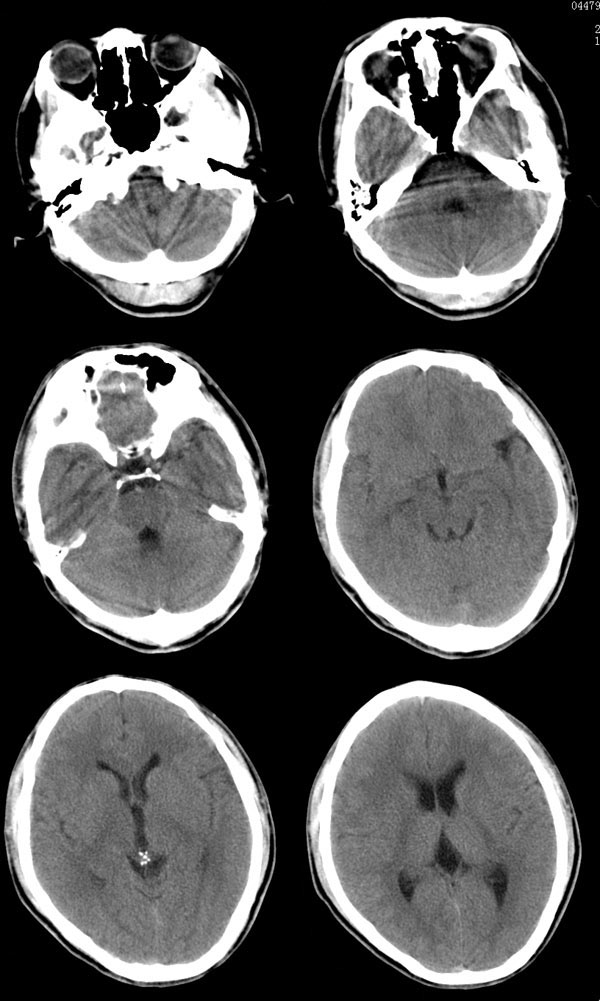

20岁男性患者,平时偶有头痛而无其他不适,现因持续头痛服药后无缓解而来院就诊。

松果体区占位继发轻度脑积水?该患者有ct资料,我已发上。

考虑松果体囊肿。